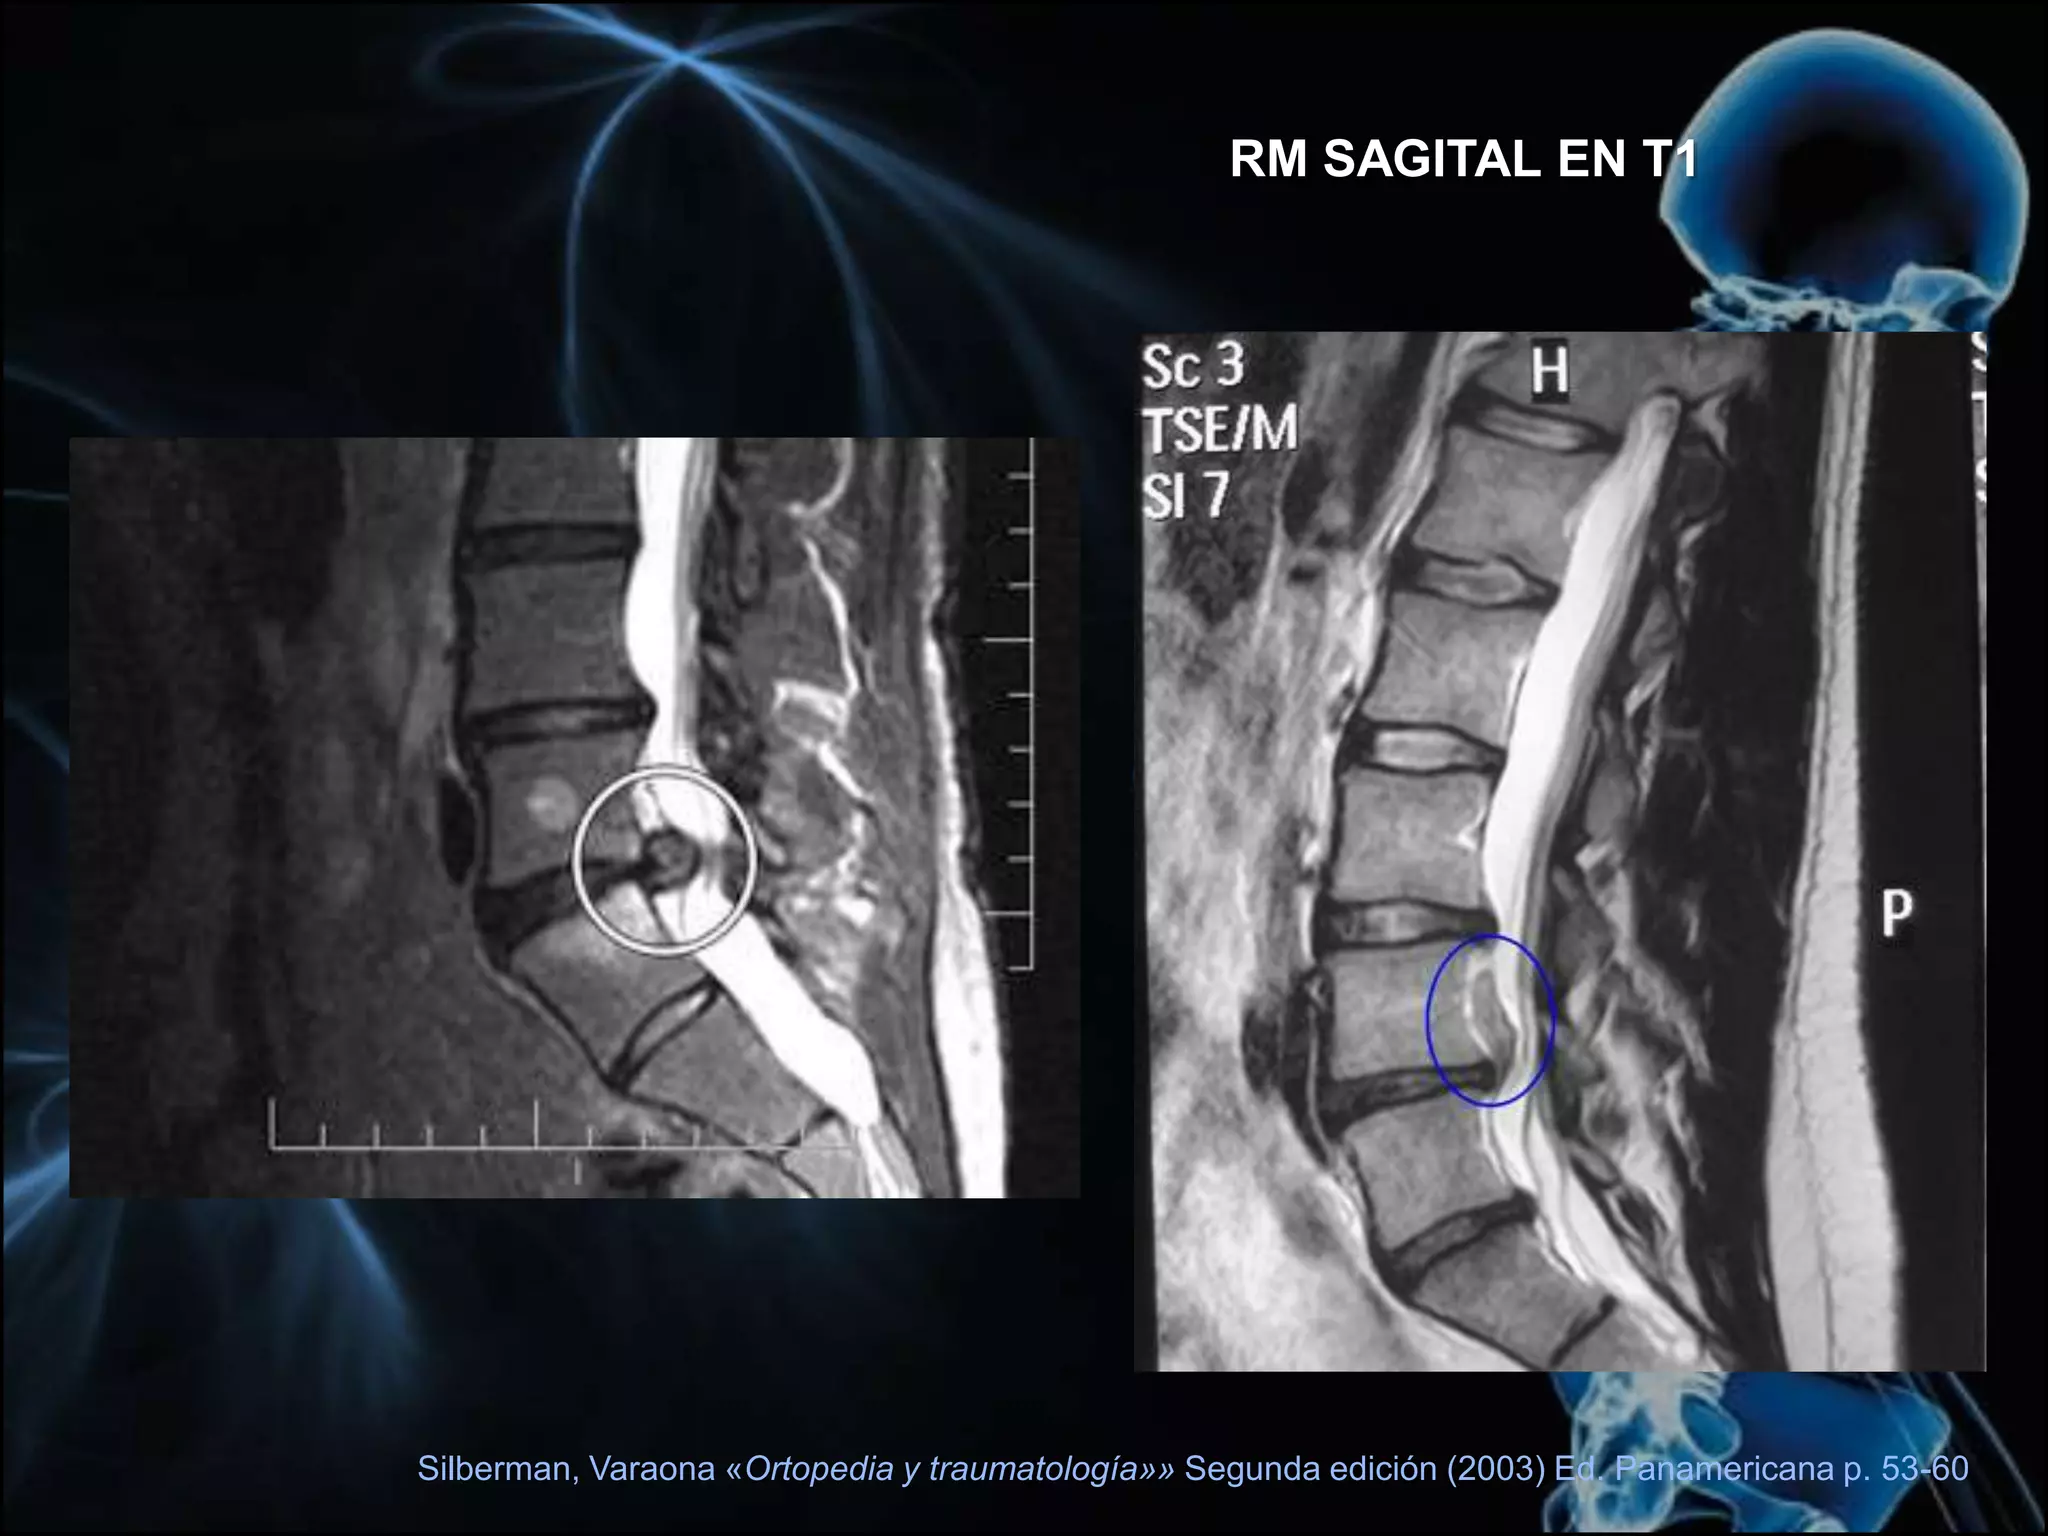

• TAC oRMN de la columna vertebral también revelarán la compresión del canal medular o la raíz espinal por parte del disco herniado.Silberman, Varaona «Ortopedia y traumatología»» Segunda edición (2003) Ed. Panamericana p. 53-60

RM SAGITAL ENT1Silberman, Varaona «Ortopedia y traumatología»» Segunda edición (2003) Ed. Panamericana p. 53-60